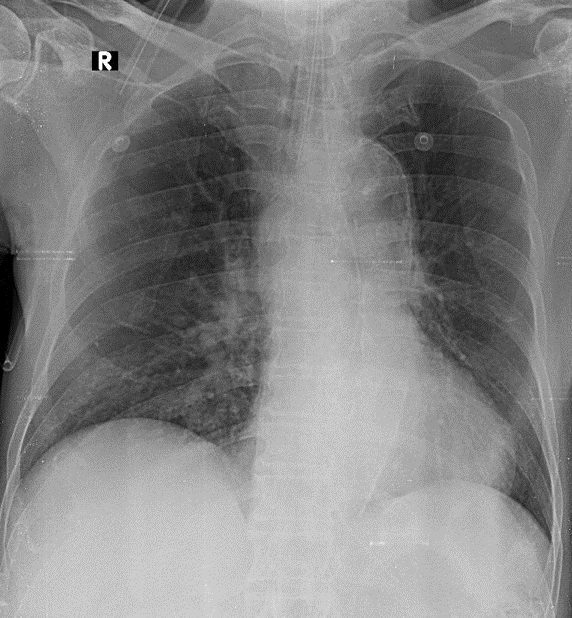

1-Đang đặc nội khí quản 2-Thâm nhiễm mô kẻ rải rác thùy dưới phổi (P) 3-Cung động mạch chủ dãn 4-Cung động mạch chủ đóng vôi 5-Tim trái lớn { dày thất trái}